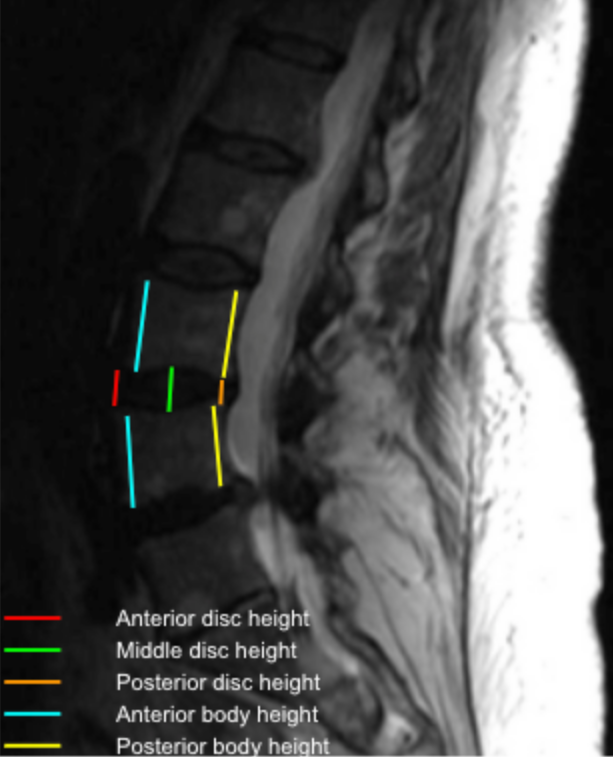

The Disc-Height Index (DHI) is a normalized metric that quantifies intervertebral disc height relative to adjacent vertebral body height. By expressing disc height as a ratio, DHI minimizes magnification and patient-size variability and serves as a sensitive marker for disc degeneration, collapse, and segmental instability.

•  Identify the disc level to be evaluated on the mid-sagittal MRI.

•  Measure disc height at three locations:

• Anterior disc height (A)

• Middle disc height (M)

• Posterior disc height (P)

• Calculate the mean disc height (DH):

DH = (A + M + P)/3

• Measure the heights of the vertebral bodies immediately above (V₁) and below (V₂) the disc at their midpoints.

• Calculate the Disc-Height Index (DHI):

DHI = DH/(V1 + V2)/2